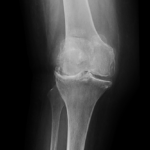

Your doctor will diagnose osteoarthritis based on the medical history, physical examination, and X-rays.

X-rays typically show a narrowing of the joint space in the arthritic knee.